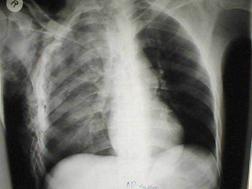

Traumatism toracic deschis Hemotorace stang masiv

Hemotorace stang masiv Hemotorace stang masiv

Hemotorace

drept masiv Hemotorace stang

Imagine CT Radiografie efectuata in ortostatism